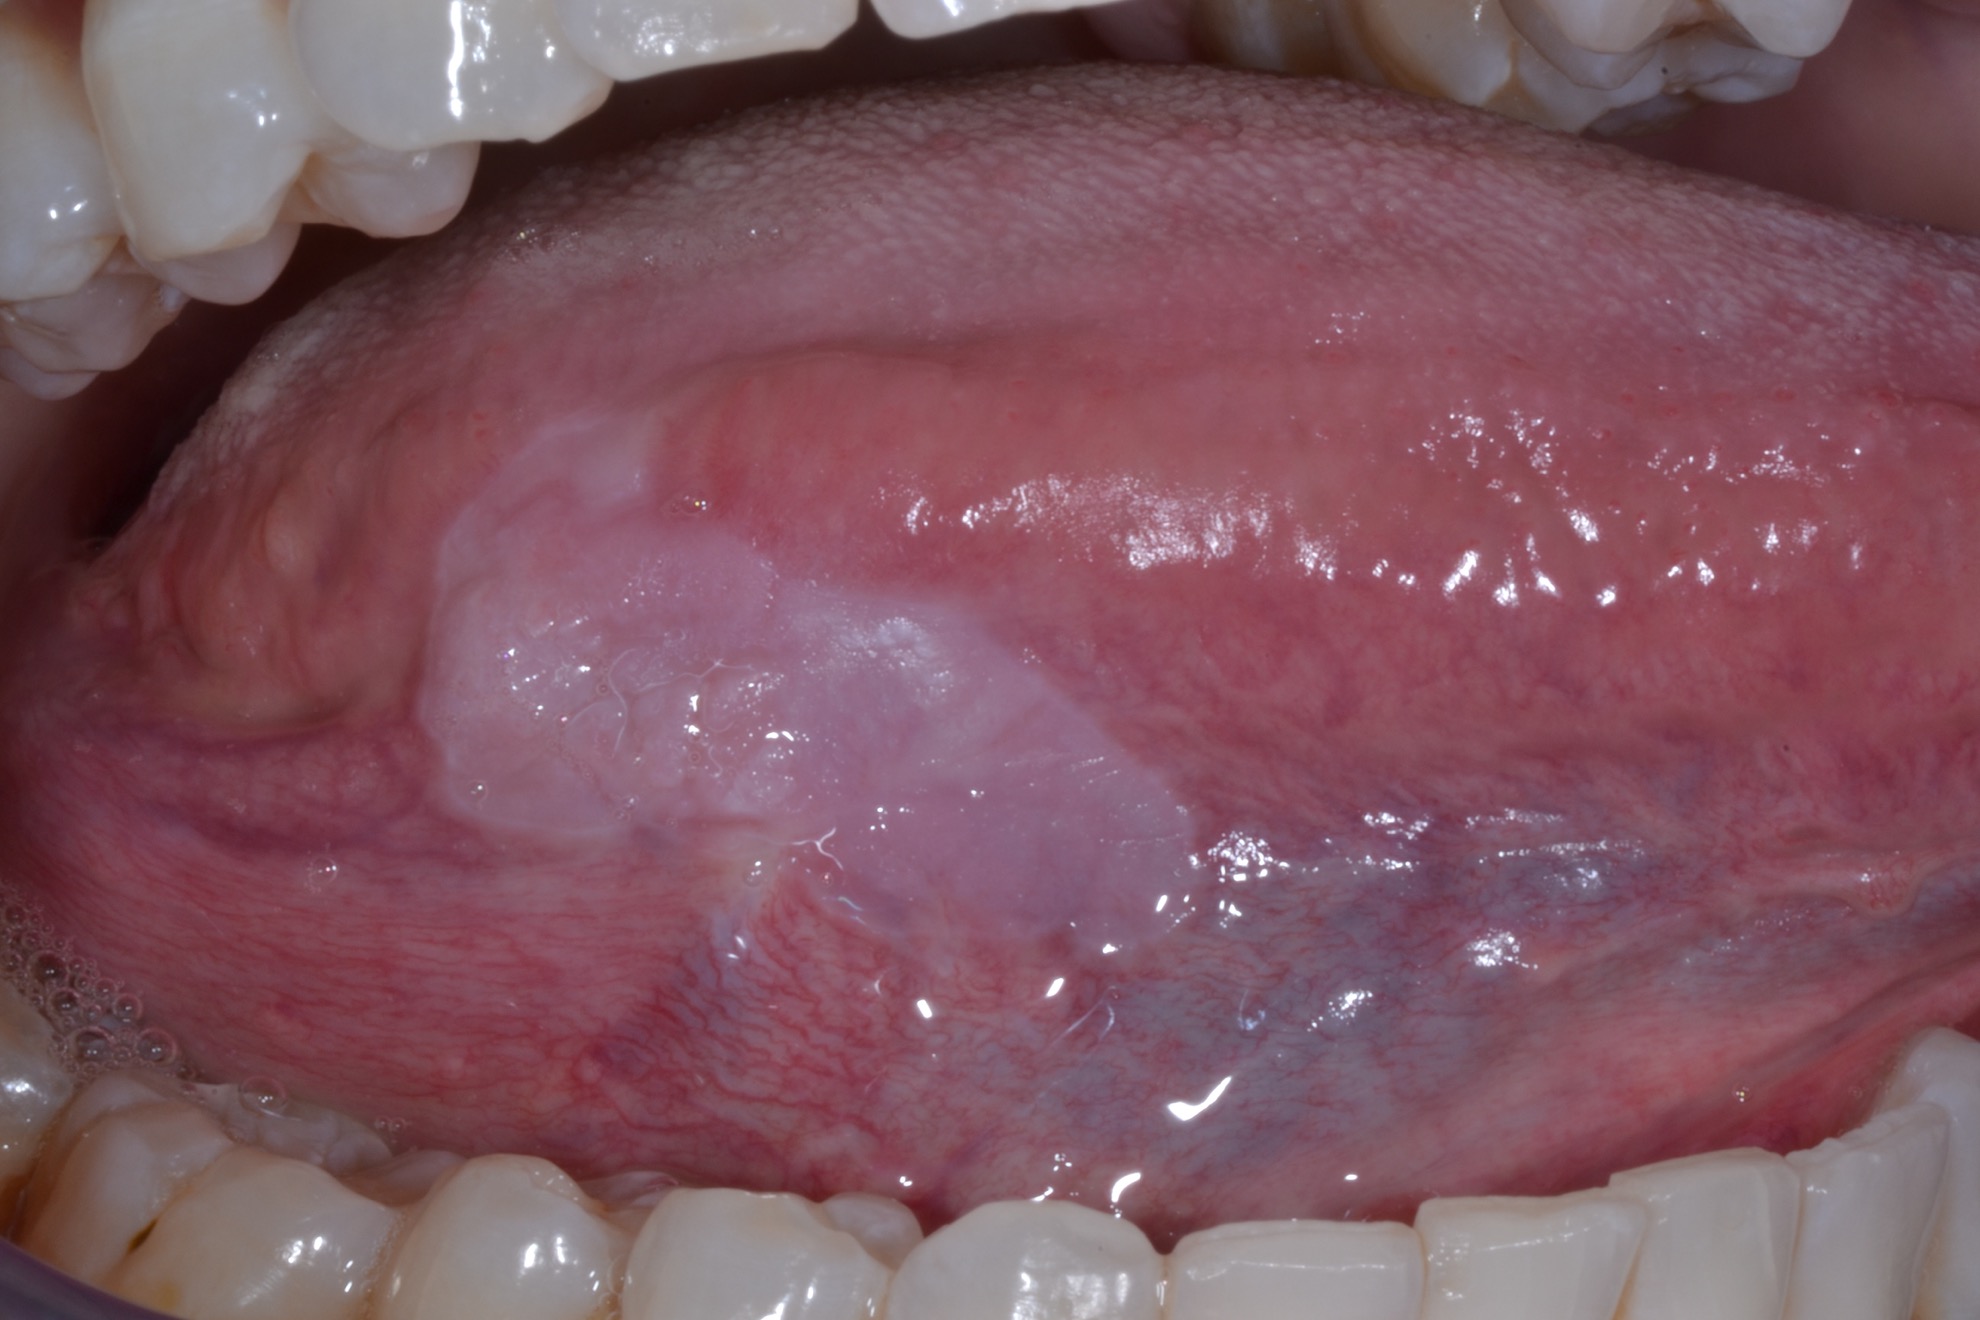

White Spots On Gums Leukoplakia . Leukoplakia is a condition involving thickened white patches on the mucous membranes (lining) of the mouth, gums, and/or. Leukoplakia patches on your tongue, gums, roof of your mouth, or the inside of your cheeks may be: If you accidentally bite the inside of your cheek or burn the roof of your. The patches don’t hurt but they don’t. They may thicken or harden overtime, and they. They are typically harmless, although some doctors think they are precancerous. Leukoplakia describes white patches on the roof of the mouth, tongue, and gums. This mouth condition appears as thick, white patches on the gums, the cheeks and the bottom of the mouth that cannot be scraped. Leukoplakia are small white patches that appear on the gums, the insides of the cheeks, the bottom of the mouth, and the tongue. Leukoplakia is a condition that creates white patches on your tongue, gums or the inside of your cheeks. But not every white patch in the mouth is leukoplakia.

If you accidentally bite the inside of your cheek or burn the roof of your. Leukoplakia describes white patches on the roof of the mouth, tongue, and gums. They may thicken or harden overtime, and they. They are typically harmless, although some doctors think they are precancerous. But not every white patch in the mouth is leukoplakia. Leukoplakia are small white patches that appear on the gums, the insides of the cheeks, the bottom of the mouth, and the tongue. The patches don’t hurt but they don’t. Leukoplakia is a condition involving thickened white patches on the mucous membranes (lining) of the mouth, gums, and/or. This mouth condition appears as thick, white patches on the gums, the cheeks and the bottom of the mouth that cannot be scraped. Leukoplakia is a condition that creates white patches on your tongue, gums or the inside of your cheeks.

White Spots On Gums Leukoplakia Leukoplakia patches on your tongue, gums, roof of your mouth, or the inside of your cheeks may be: Leukoplakia patches on your tongue, gums, roof of your mouth, or the inside of your cheeks may be: This mouth condition appears as thick, white patches on the gums, the cheeks and the bottom of the mouth that cannot be scraped. If you accidentally bite the inside of your cheek or burn the roof of your. Leukoplakia describes white patches on the roof of the mouth, tongue, and gums. Leukoplakia are small white patches that appear on the gums, the insides of the cheeks, the bottom of the mouth, and the tongue. The patches don’t hurt but they don’t. But not every white patch in the mouth is leukoplakia. They may thicken or harden overtime, and they. They are typically harmless, although some doctors think they are precancerous. Leukoplakia is a condition involving thickened white patches on the mucous membranes (lining) of the mouth, gums, and/or. Leukoplakia is a condition that creates white patches on your tongue, gums or the inside of your cheeks.